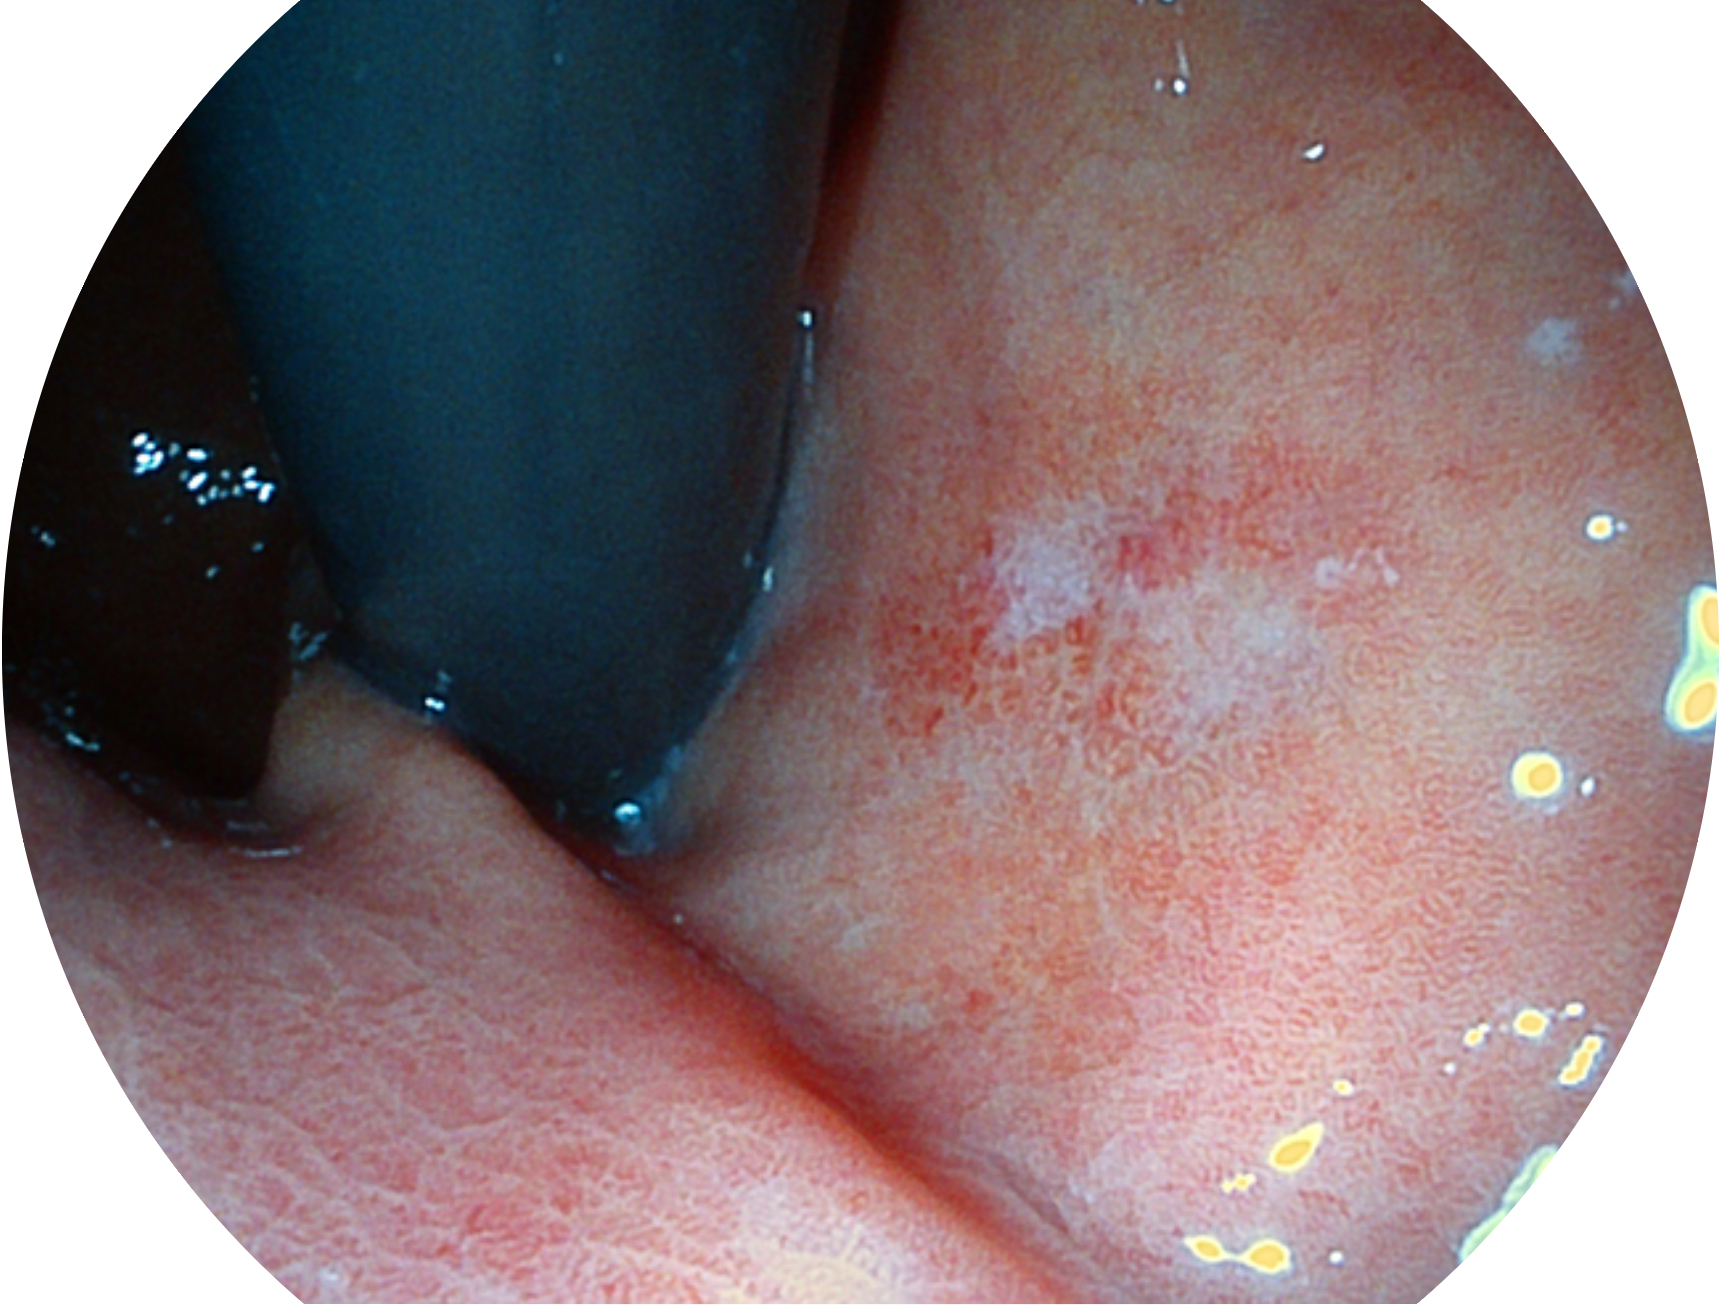

• 白光图像 VIST图像

SFI技术是结合特定光谱照明与数字光谱滤波,实现高亮度特殊光成像。染色模式下,不改变粘液、食物残渣、粪液等基本颜色,在保持与白光照明相似的图像色调的同时突显了图像颜色的红白对比度,且在远距离观察的情况下具备与普通白光模式相同的图像亮度,有助于消化道疾病的大范围扫查和早癌筛查。

• 白光图像 SFI图像